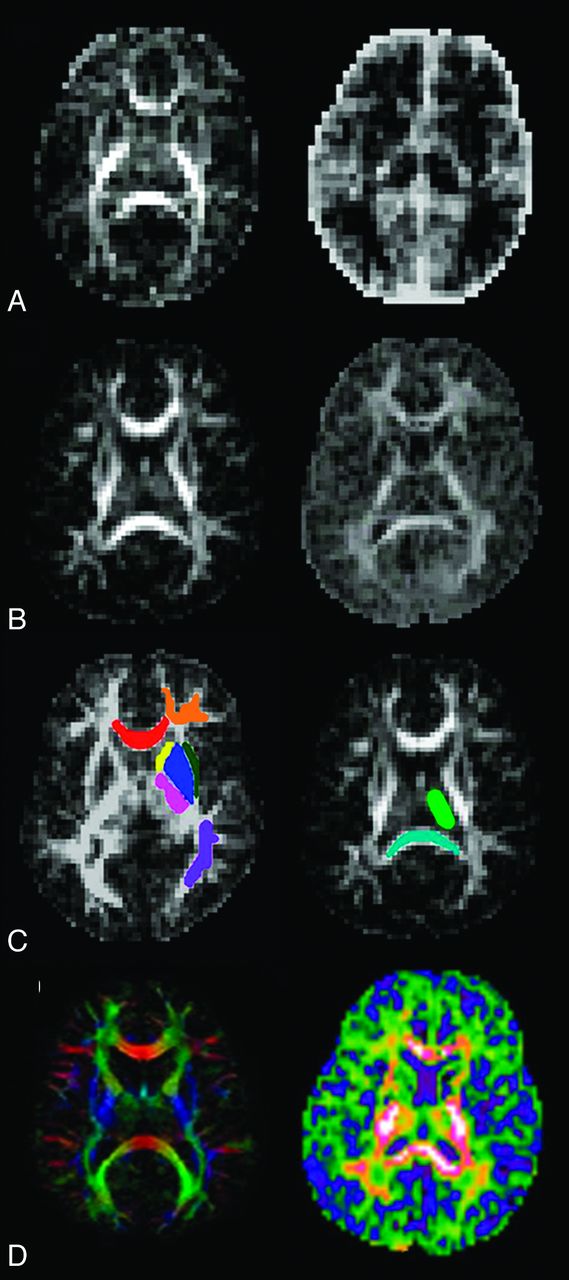

DKI data were processed by using in-house software called the Diffusional Kurtosis Estimator (http://www.nitrc.org/projects/dke). Subsequently, the diffusion and kurtosis tensors were calculated on a voxel-by-voxel basis to produce skull-stripped parametric gray-scale maps for FA and MK.19,25 Sample transaxial sections from FA and MK maps for the youngest and oldest subjects are portrayed in Fig 1A and -B.

A, Transaxial FA (left) and MK (right) maps at birth. B, Transaxial FA (left) and MK (right) maps at 4 years 7 months. C, Examples of VOIs drawn on transaxial FA maps over the genu (red), frontal WM (orange), parietal WM (purple), putamen (blue), anterior IC (yellow), posterior IC (pink), external capsule (dark green), thalamus (light green), and splenium (cyan). D, Transaxial FA (left) and MK (right) color maps.

Using MRIcron (http://www.sph.sc.edu/comd/rorden/mricro.html), we drew VOIs directly on multiple FA map transverse sections for volumetric analysis. VOIs were drawn on 9 different anatomic WM and GM structures, including the genu and splenium of the corpus callosum, frontal WM, parietal WM, anterior and poster limbs of the internal capsule (IC), external capsule, thalamus, and putamen (Fig 1C). VOI drawing was performed by a neuroradiology fellow, fourth-year radiology resident, and a second-year medical student. To control for interobserver variability, we assigned each of these investigators to draw all of the VOIs for any given anatomic structure for all the subjects. All VOIs were later carefully reviewed by a single board-certified pediatric neuroradiologist to further minimize interobserver variability. VOIs were then applied to the parametric maps in Matlab (MathWorks, Natick, Massachusetts) to calculate the mean FA and MK values for each VOI.